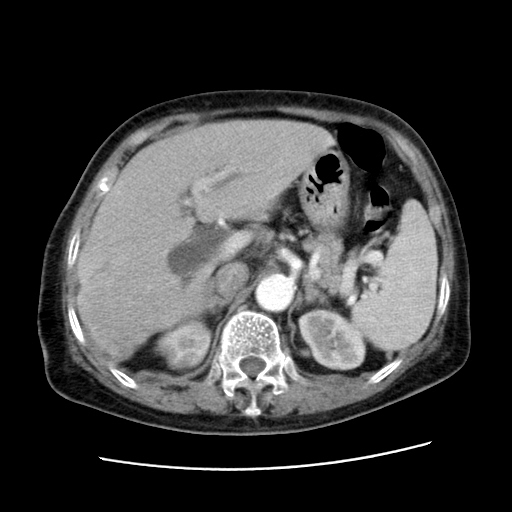

女,77.无不适

肝脏变异、异位胆囊,肝右叶肝内胆管结石并肝内胆管扩张。

肝右叶肝内胆管结石并肝内胆管扩张。

肝右叶肝内胆管结石并肝内胆管扩张

胆总管扩张

肝右叶肝内胆管结石并肝内胆管扩张。胆总管下段梗阻,考虑壶腹部占位。

右侧肝内胆管局限性扩张,其内密度不均匀,扩张的胆管壁增厚,考虑肝内胆管炎合并结石可能性大

肝右叶肝内胆管结石并肝内胆管扩张。胆总管下段梗阻,考虑壶腹部占位。支持